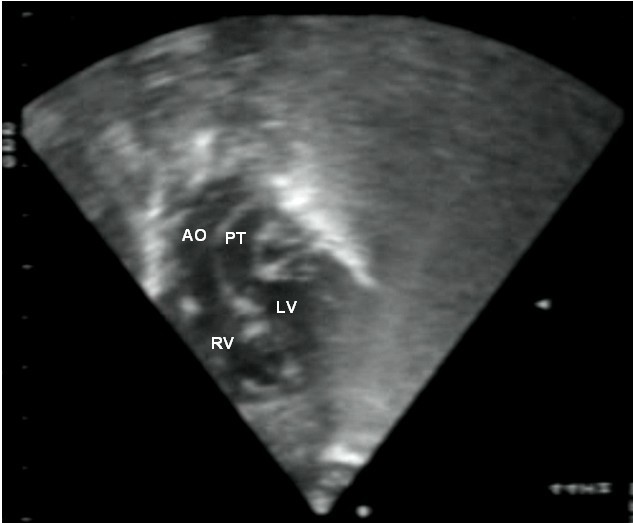

심장 초음파 검사는 심장의 구조와 기능을 정확하게 평가하는 초음파 검사이며, TGA의 특징을 보여줄 수 있다. 이 검사를 통해 TGA를 확진할 수 있다.[3]

약어: LV 및 RV=좌심실 및 우심실, PT=폐동맥, VSD=심실 중격 결손, PS=폐동맥 협착.]]